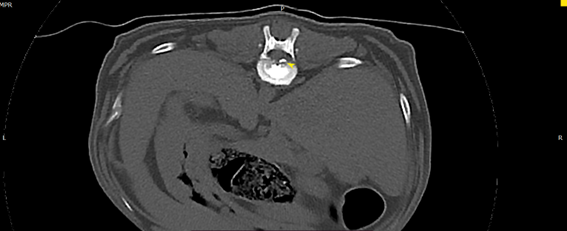

臘腸狗狗 椎間盤疾病 ivdd

懷疑椎間盤疾病的狗狗 常見背痛、腳無力、癱瘓,需要由專業的獸醫師神經學檢查

評估定位病灶區域 搭配電腦斷層掃描來決定手術位置及手術方式